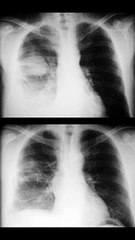

Tumor de hueso. Condrosarcoma.